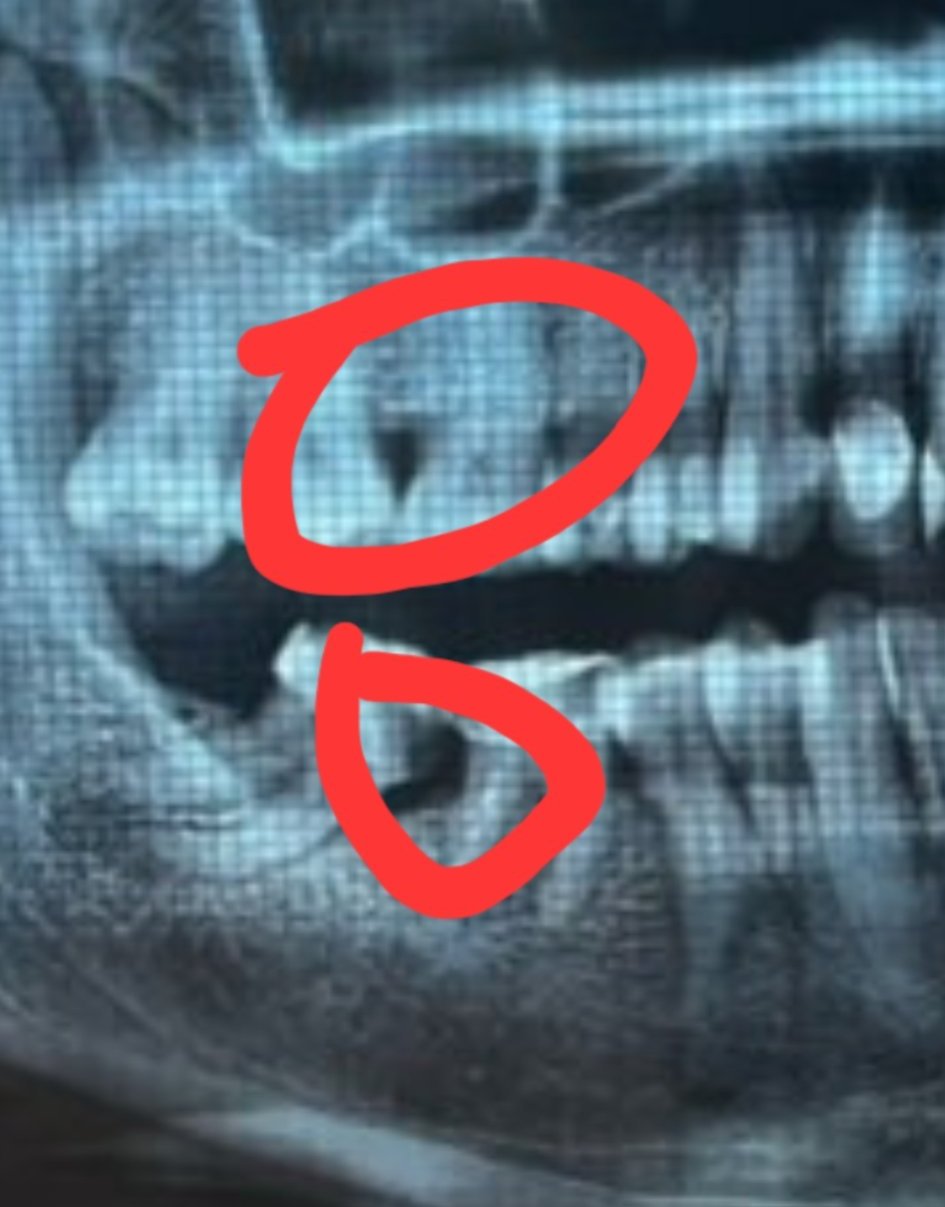

teta75 тук има ли стопена кост

Не съм зъболекар..но има стопена според мен.

Черните триъгълници са липса на кост